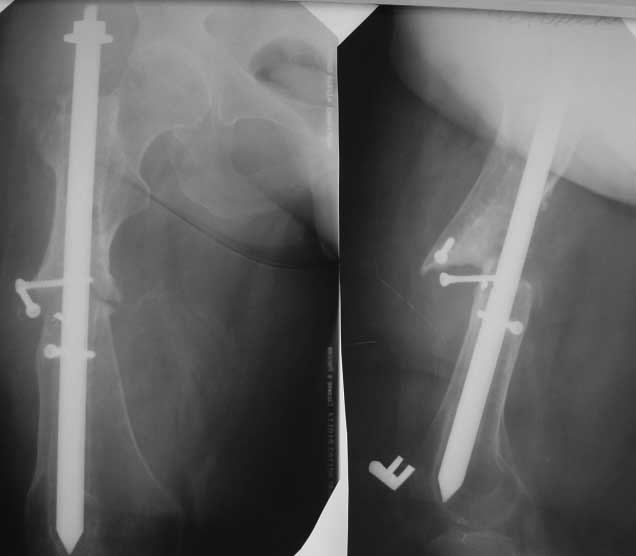

Ложный сустав бедра.

Обратилась пациентка 55 лет. Из анамнеза - травма 6 лет назад, ДТП - переломы С/3 правого

бедра, обеих голеней, правого плеча, правой ключицы. Оперирована - остеосинтез голеней

аппаратами Илизарова - консолидация, остеосинтез перелома плеча пластиной - формирование

ложного сустава, реоперация - удаление пластины, костная аутопластика, аппарат Илизарова

- консолидация. Перелом бедра первично стабилизирован интрамедуллярно 4 -х гранным

стержнем типа ЦИТО - формирование ложного сустава. Оперирована повторно 4 года назад-

стержнем ЦИТО диаметром 15 мм с попыткой блокировки и компрессии кустарным

способом+костная аутопластика костью с гребня подвздошной кости. Обратилась вот с такой

Р-гр картиной. На сегодняшний день абсолютное укорочение 8 см, патологическая

подвижность, нога не опорная, контрактуры коленного т\бедренного суставов. Что скажет

уважаемое сообщество?